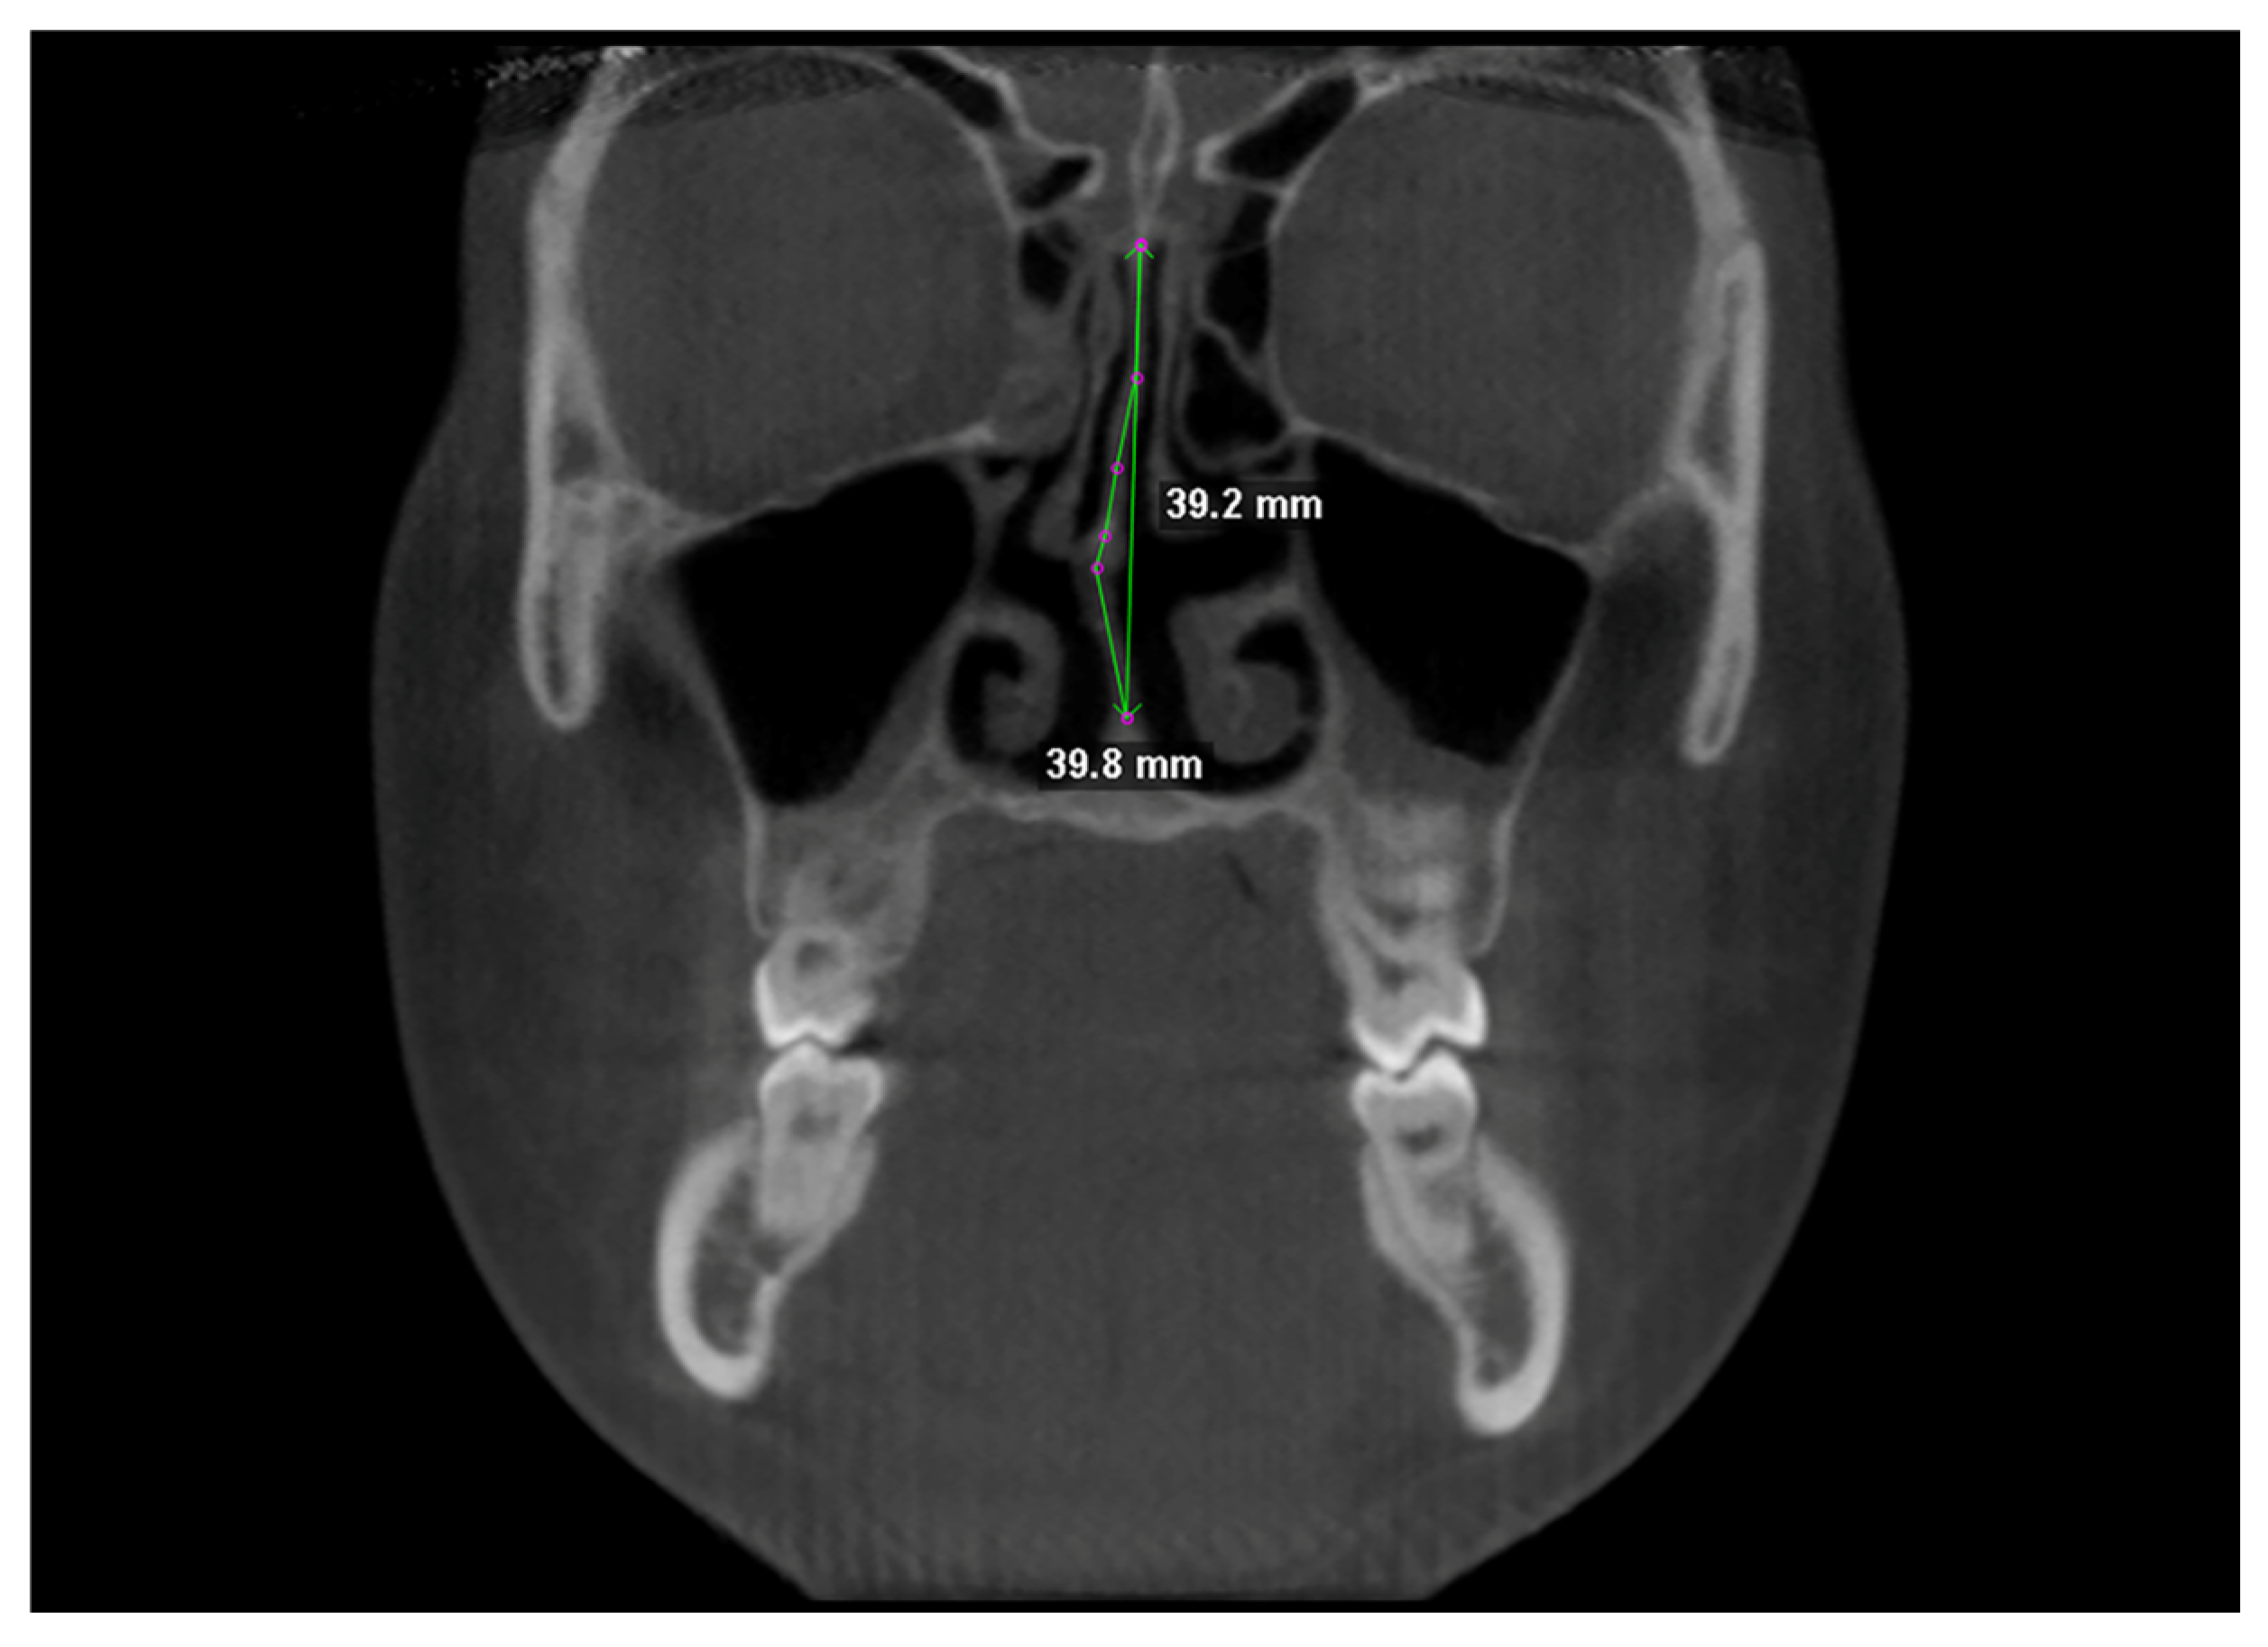

Nasal septum was traced at two different levels in coronal view, i.e., at the Crista Galli, and (2) at the Anterior Nasal Spine (Figure 3). Tracing was performed in the cranio-caudal direction by placing points 1–2 mm apart [1]. NSD was calculated according to the “degree of tortuosity” or the ratio of length of the curve to the length of an imaginary line in the mid sagittal plane [1], expressed with the formula:

Figure 3.

Linear measurements for calculating the tortuosity ratio (TR).

Both the actual length of the septum and its ideal length were used to calculate TR values [26].